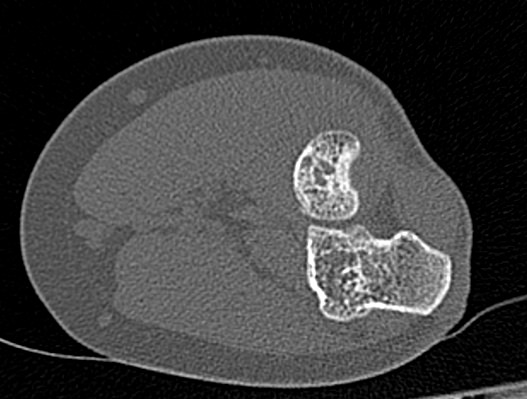

Одним из наиболее информативных методов исследования локтевого сустава является мультиспиральная компьютерная томография. Мультиспиральная КТ локтевого сустава позволяет оценить состояние костных структур и капсульно-связочного аппарата сустава. В отличие от обычного рентгена, при котором изображения накладываются друг на друга, мультиспиральная компьютерная томография с помощью рентгеновских лучей сканирует исследуемую область в разных плоскостях, делая множество тончайших срезов и преобразуя данные в цифровые трехмерные изображения.

Костная ткань хорошо поглощает рентгеновские лучи, поэтому кости ярко визуализируются на снимках КТ. Компьютерная томография в первую очередь востребована в ортопедии и травматологии. Методика широко применяется для диагностики костной патологии. С помощью КТ можно оценить плотность костной ткани и выявить косвенные признаки остеопороза. В случае перелома можно определить точную локализацию костных отломков, что особенно важно при планировании оперативного вмешательства и в послеоперационном периоде для наблюдения за процессом восстановления. КТ также помогает в диагностике различных артритов и артрозов.